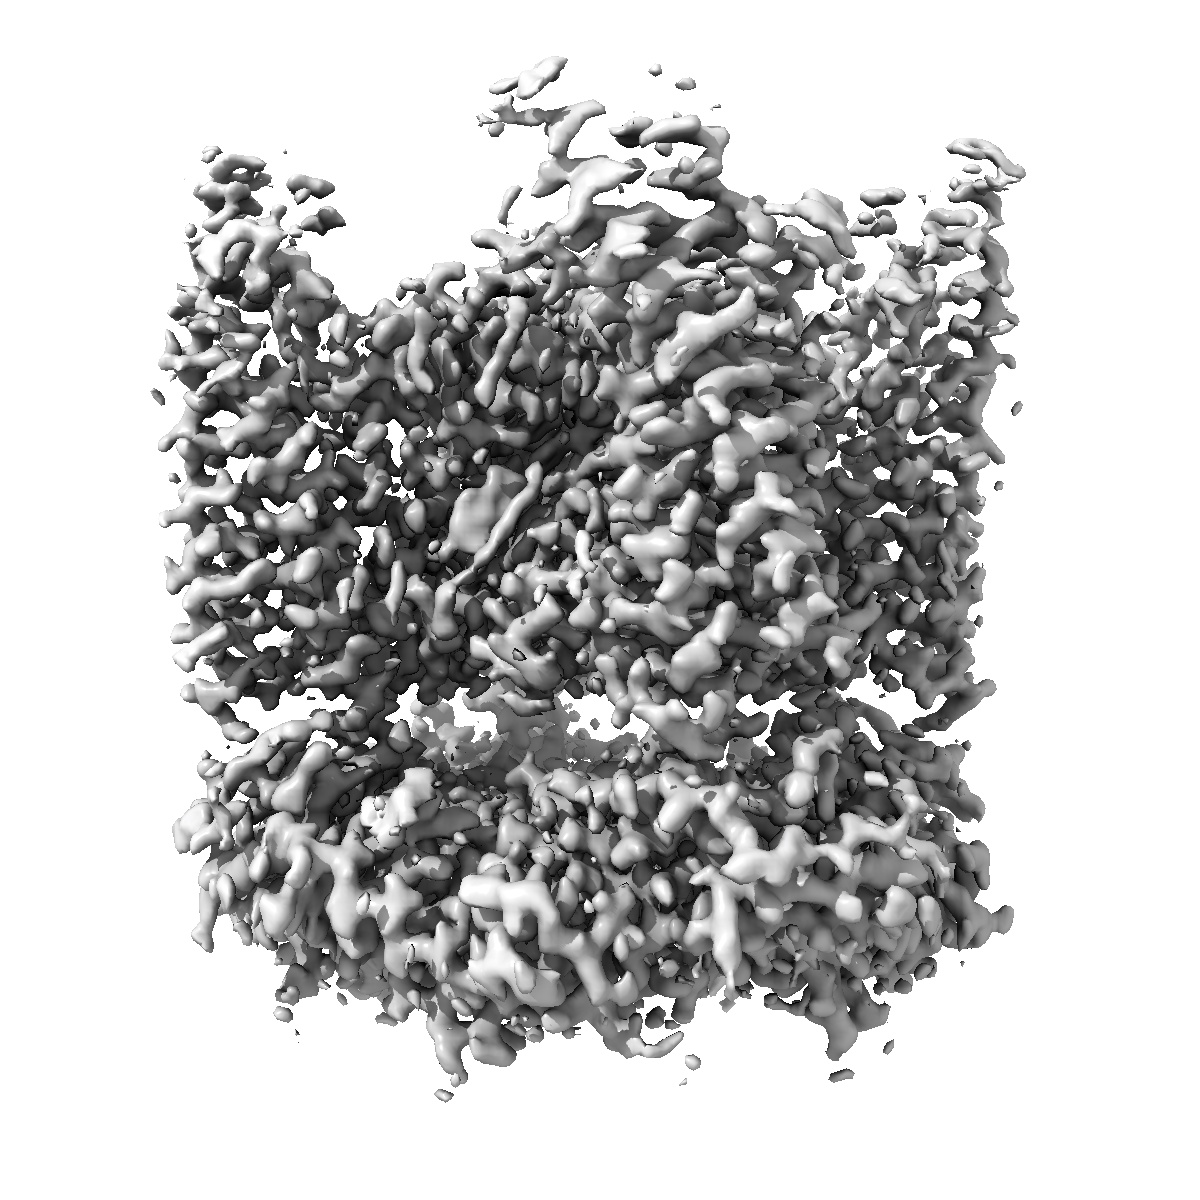

TRPML1 in complex with compound 11

Single-particle2.1 Å

High throughput cryo-EM provides structural understanding for modulators of the lysosomal ion channel TRPML1.

(2025) Structure , 33 , 1374 - 1385.e7